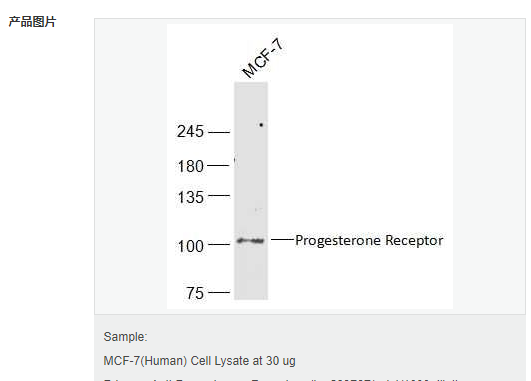

| 英文名稱 | Progesterone Receptor |

| 中文名稱 | 孕激素受體抗體 |

| 產(chǎn)品應用 | WB=1:500-2000 IHC-P=1:100-500 IHC-F=1:100-500 Flow-Cyt=1ug/Test ICC=1:100-500 IF=1:100-500 (石蠟切片需做抗原修復) not yet tested in other applications. optimal dilutions/concentrations should be determined by the end user. |

| 分 子 量 | 103kDa |